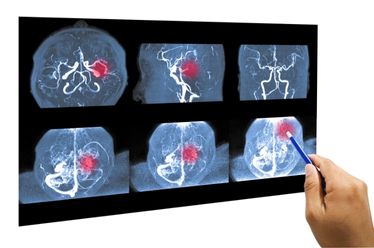

Diagnóstico Preciso para o Melhor Tratamento

O diagnóstico começa com uma avaliação clínica detalhada, onde o médico analisa o histórico do paciente e realiza testes físicos. A confirmação, no entanto, é feita através de exames de imagem, sendo a Ressonância Magnética o padrão-ouro. Ela permite visualizar com clareza a localização da hérnia, o grau de compressão do nervo e ajuda a descartar outras condições com sintomas semelhantes.